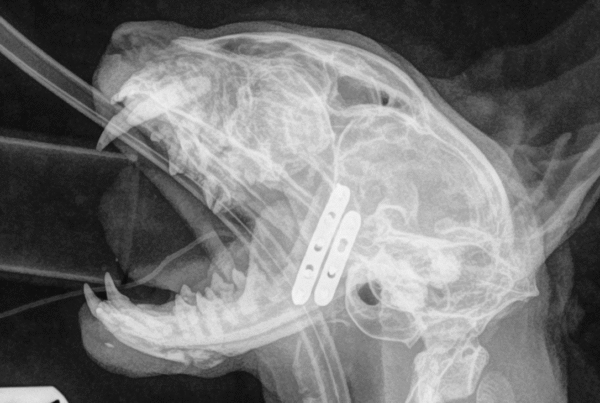

Lula’s Remarkable Recovery After a Severe Stick Injury